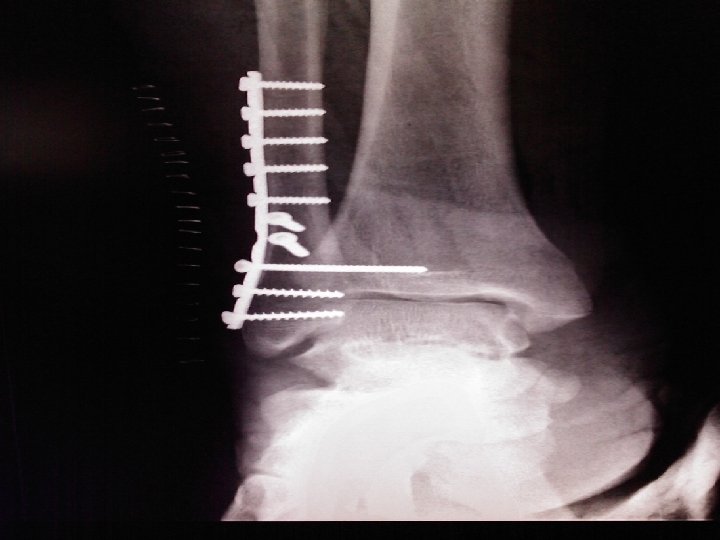

Tratamiento quirúrgico: • Bajo anestesia raquídea y control fluoroscópico • Reducción abierta y osteosíntesis con dos tornillos de compresión y placa • Se coloca tornillo transindesmal tricortical

Evolución : • Favorable clínica y radiológicamente • Al cuarto día egresa, con posterior revisión y control radiológico a los 7 días